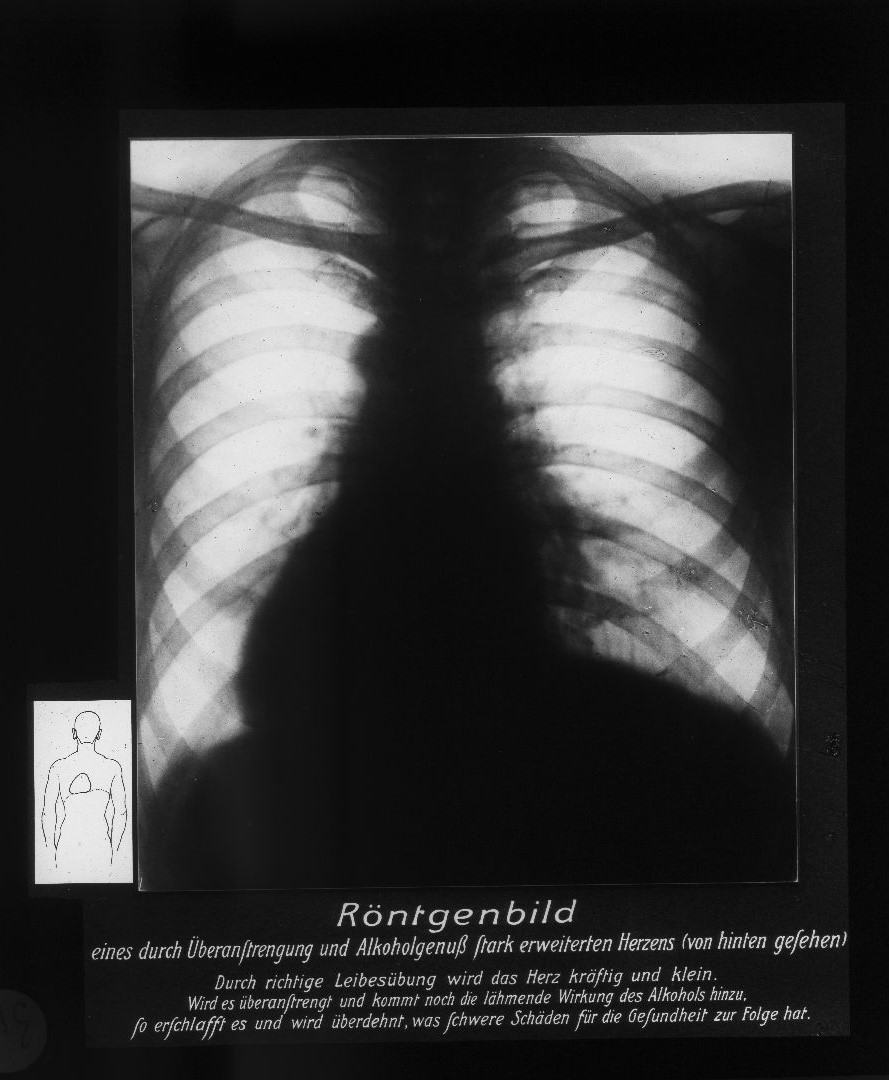

Von der Fettleber bis zur Schrumpfniere. Monokausale Zusammenhänge und Schuldzuweisung

„Der Alkohohol – Dein Feind!“ Auch der Diskurs über die körperliche Schädigung des Alkohols zielte in der sozialdemokratischen Antialkoholpolitik auf die Gesundheit des „Volkes“ ab. Die Bevölkerung sollte zur Abstinenz erzogen werden, Gesundheit war moralische Arbeit und Abweichung von der Moral hatte Krankheiten zur Folge. Der Terminus „Trinker“ war unscharf: Es erfolgte keine Unterscheidung zwischen Alkoholmissbrauch, Alkoholabhängigkeit und gelegentlichem Alkoholkonsum. Die abschreckenden Bilder degenerierter innerer Organe und Medizinalstatistiken waren ein Appell an die Moral.